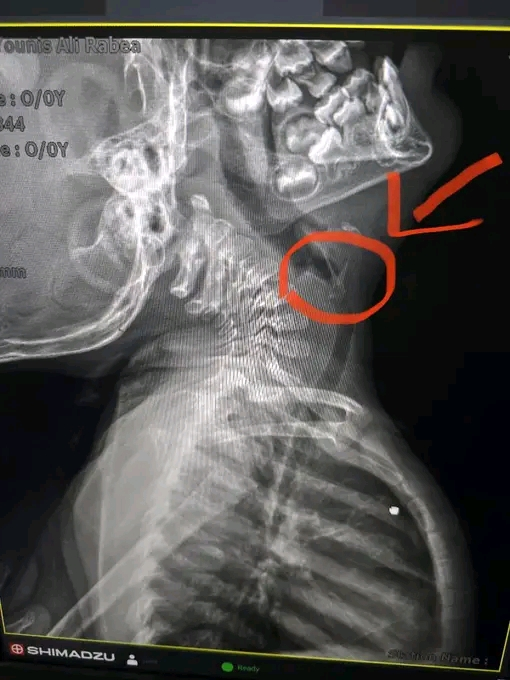

وأوضح الدكتور مجدي امين القاضي، عميد كلية الطب البشري ورئيس مجلس إدارة المستشفيات الجامعية، أن الطفل كان قد حضر إلى استقبال مستشفى الطوارئ الجامعي الجديد برفقة والديه بعد ابتلاعه أو استنشاقه جسمًا غريبًا، مما تسبب له في صعوبة بالتنفس، وبعد الفحص الإكلينيكي والأشعة، تبين وجود شوكة سمكة ملتصقة بجدار القصبة الهوائية، فتم تحويل الحالة بشكل عاجل إلى غرفة عمليات الطوارئ بقسم جراحة القلب والصدر.